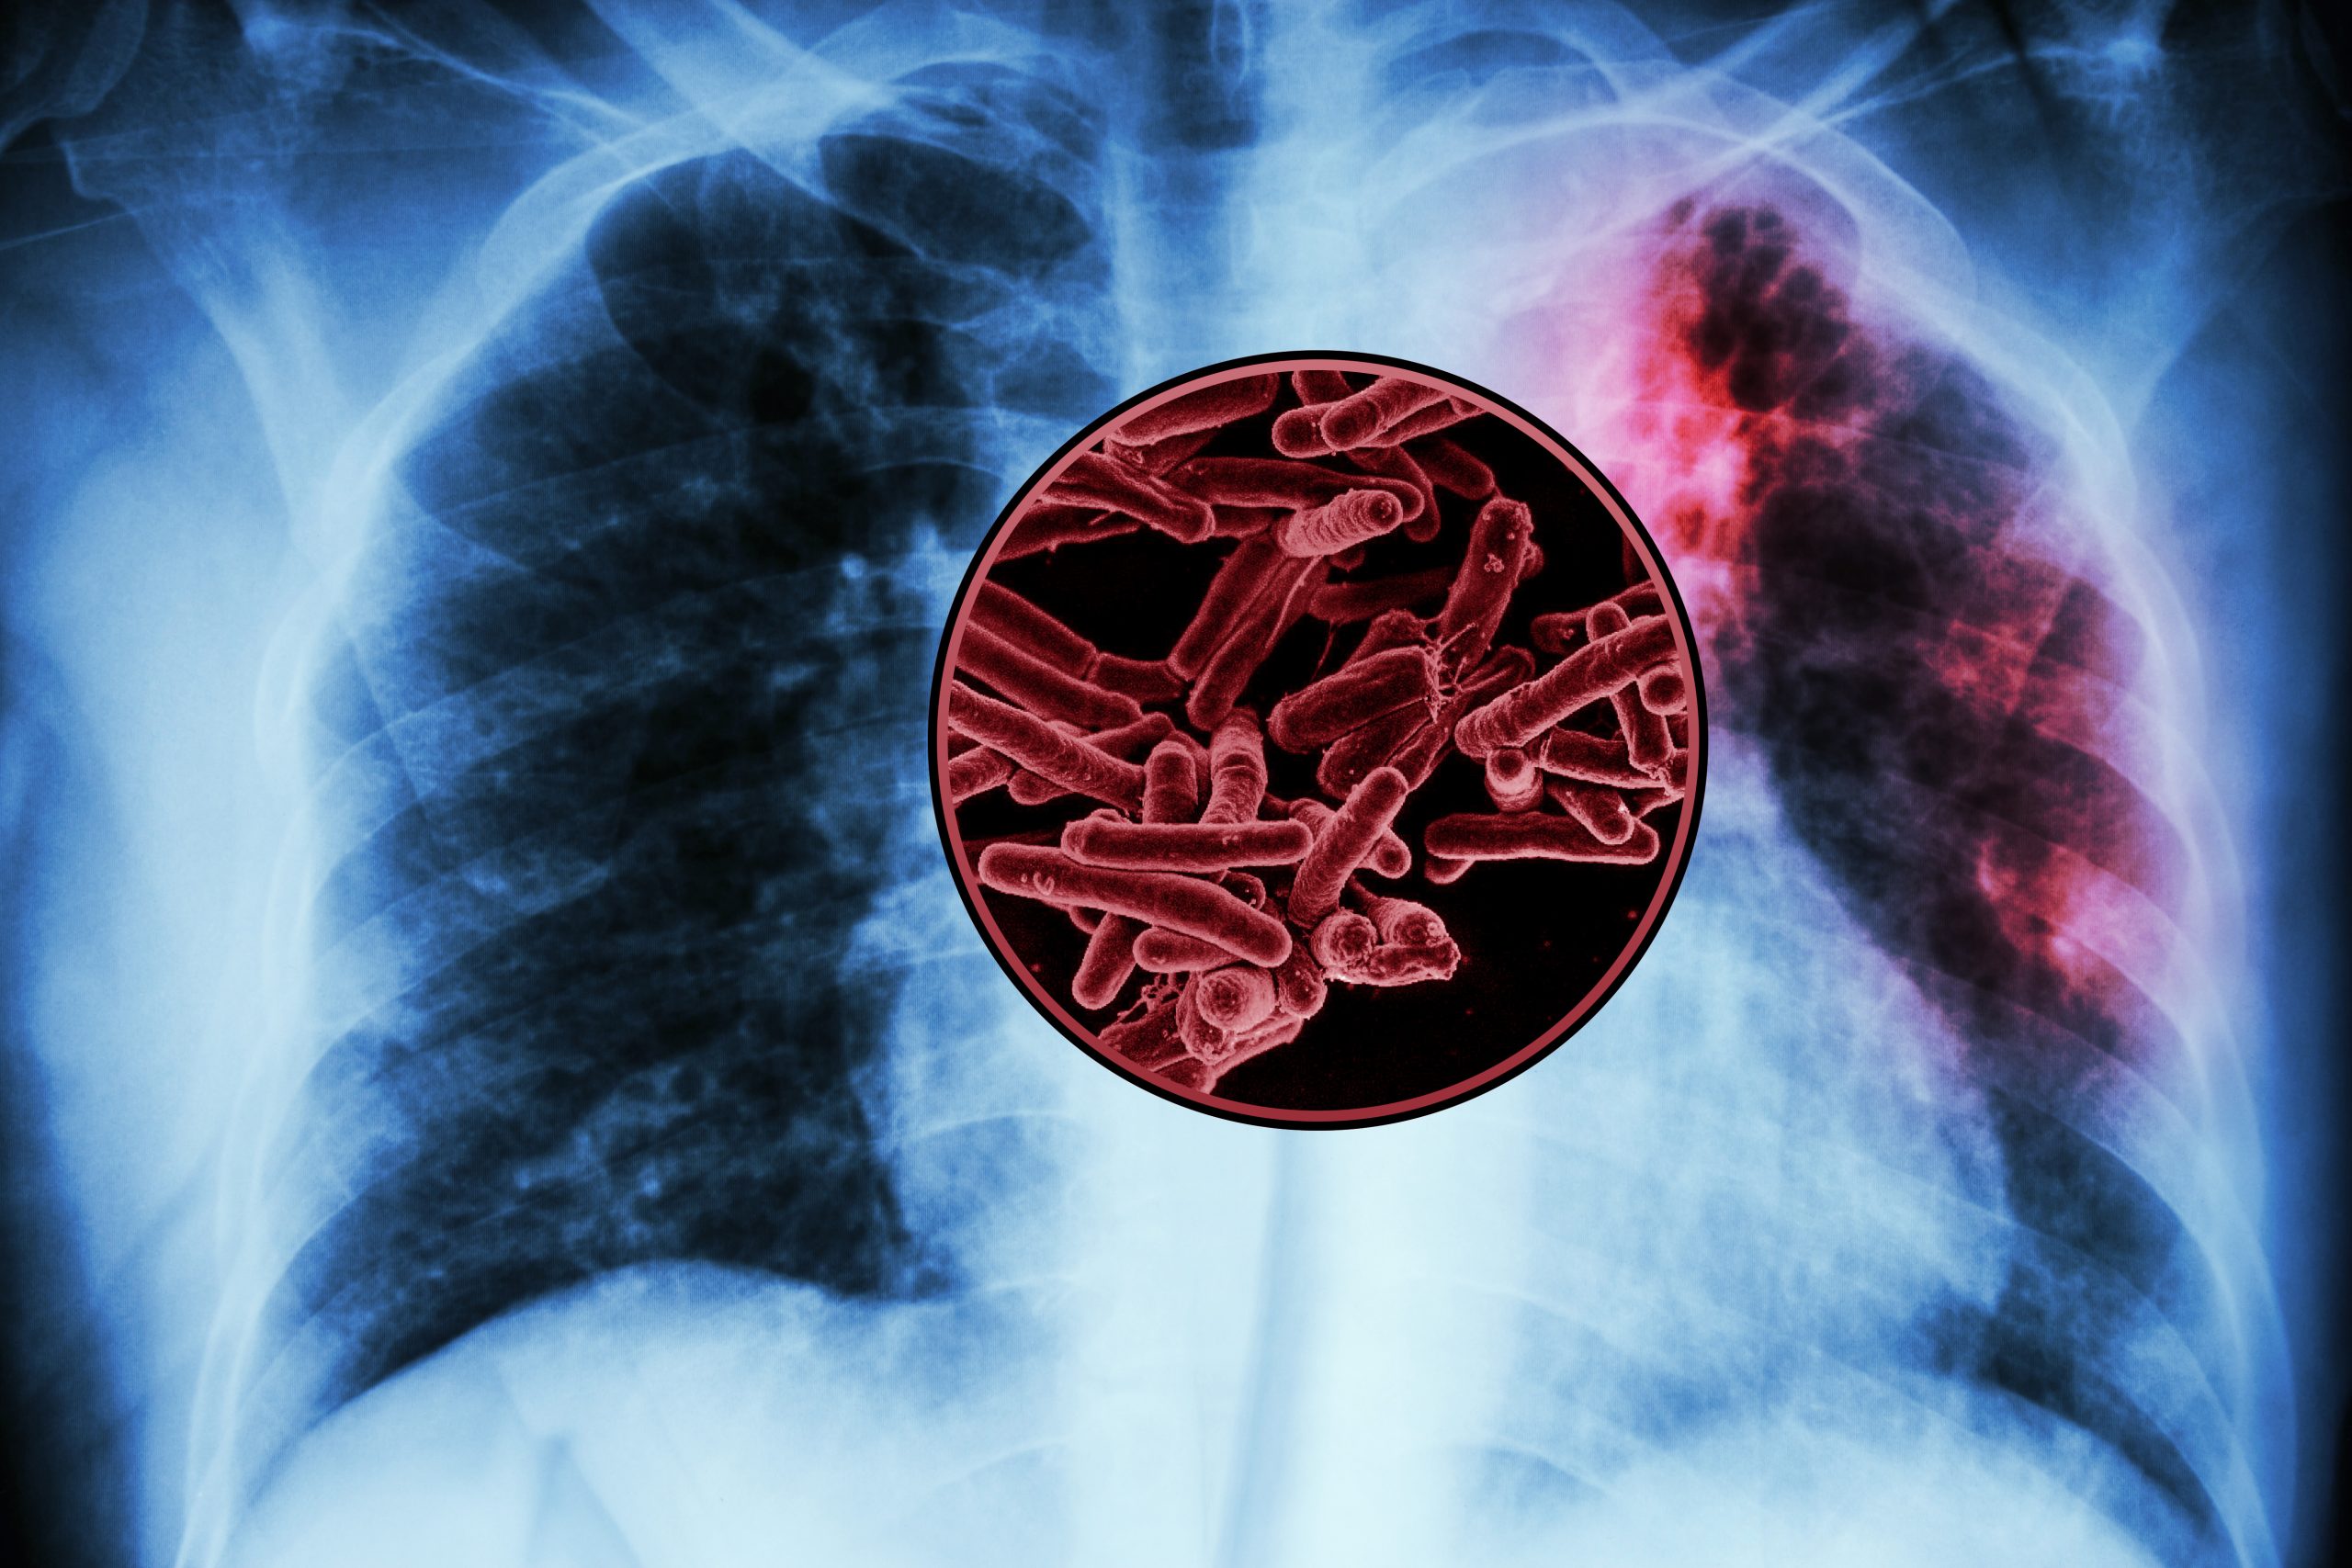

A large-scale screen of tuberculosis proteins has revealed several possible antigens that could be developed as a new vaccine for TB, the world’s deadliest infectious disease.

There is currently only one vaccine for tuberculosis, known as BCG, which is a weakened version of a bacterium that causes TB in cows. This vaccine is widely administered in some parts of the world, but it poorly protects adults against pulmonary TB. Worldwide, tuberculosis kills more than 1 million people every year.

Since the BCG vaccine was developed more than 100 years ago, no other TB vaccines have been approved for use. Mycobacterium tuberculosis produces more than 4,000 proteins, which makes it a daunting challenge to pick out proteins that might elicit a strong immune response if used as a vaccine.